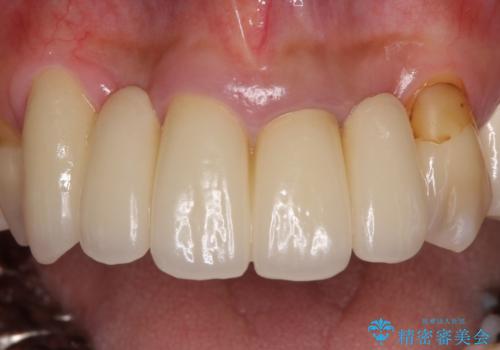

自然な仕上がりとするため、金属を使用しないオールセラミックブリッジにより補綴治療を行うこととしました。

露出していた歯根や金属の縁が見えてしまい、なかなか口を開けて笑うことができなかったのですが、歯肉の位置に縁を合わせることで自然な仕上がりとなりました。

ブリッジの隙間にものが詰まったり、空気が抜けたりすることも無くなり、話しやすさも改善することができました。

露出していた歯根が覆われるため、歯冠が長く見えてしまうことが懸念されましたが特に気になることはなく、患者様には大変満足していただきました。